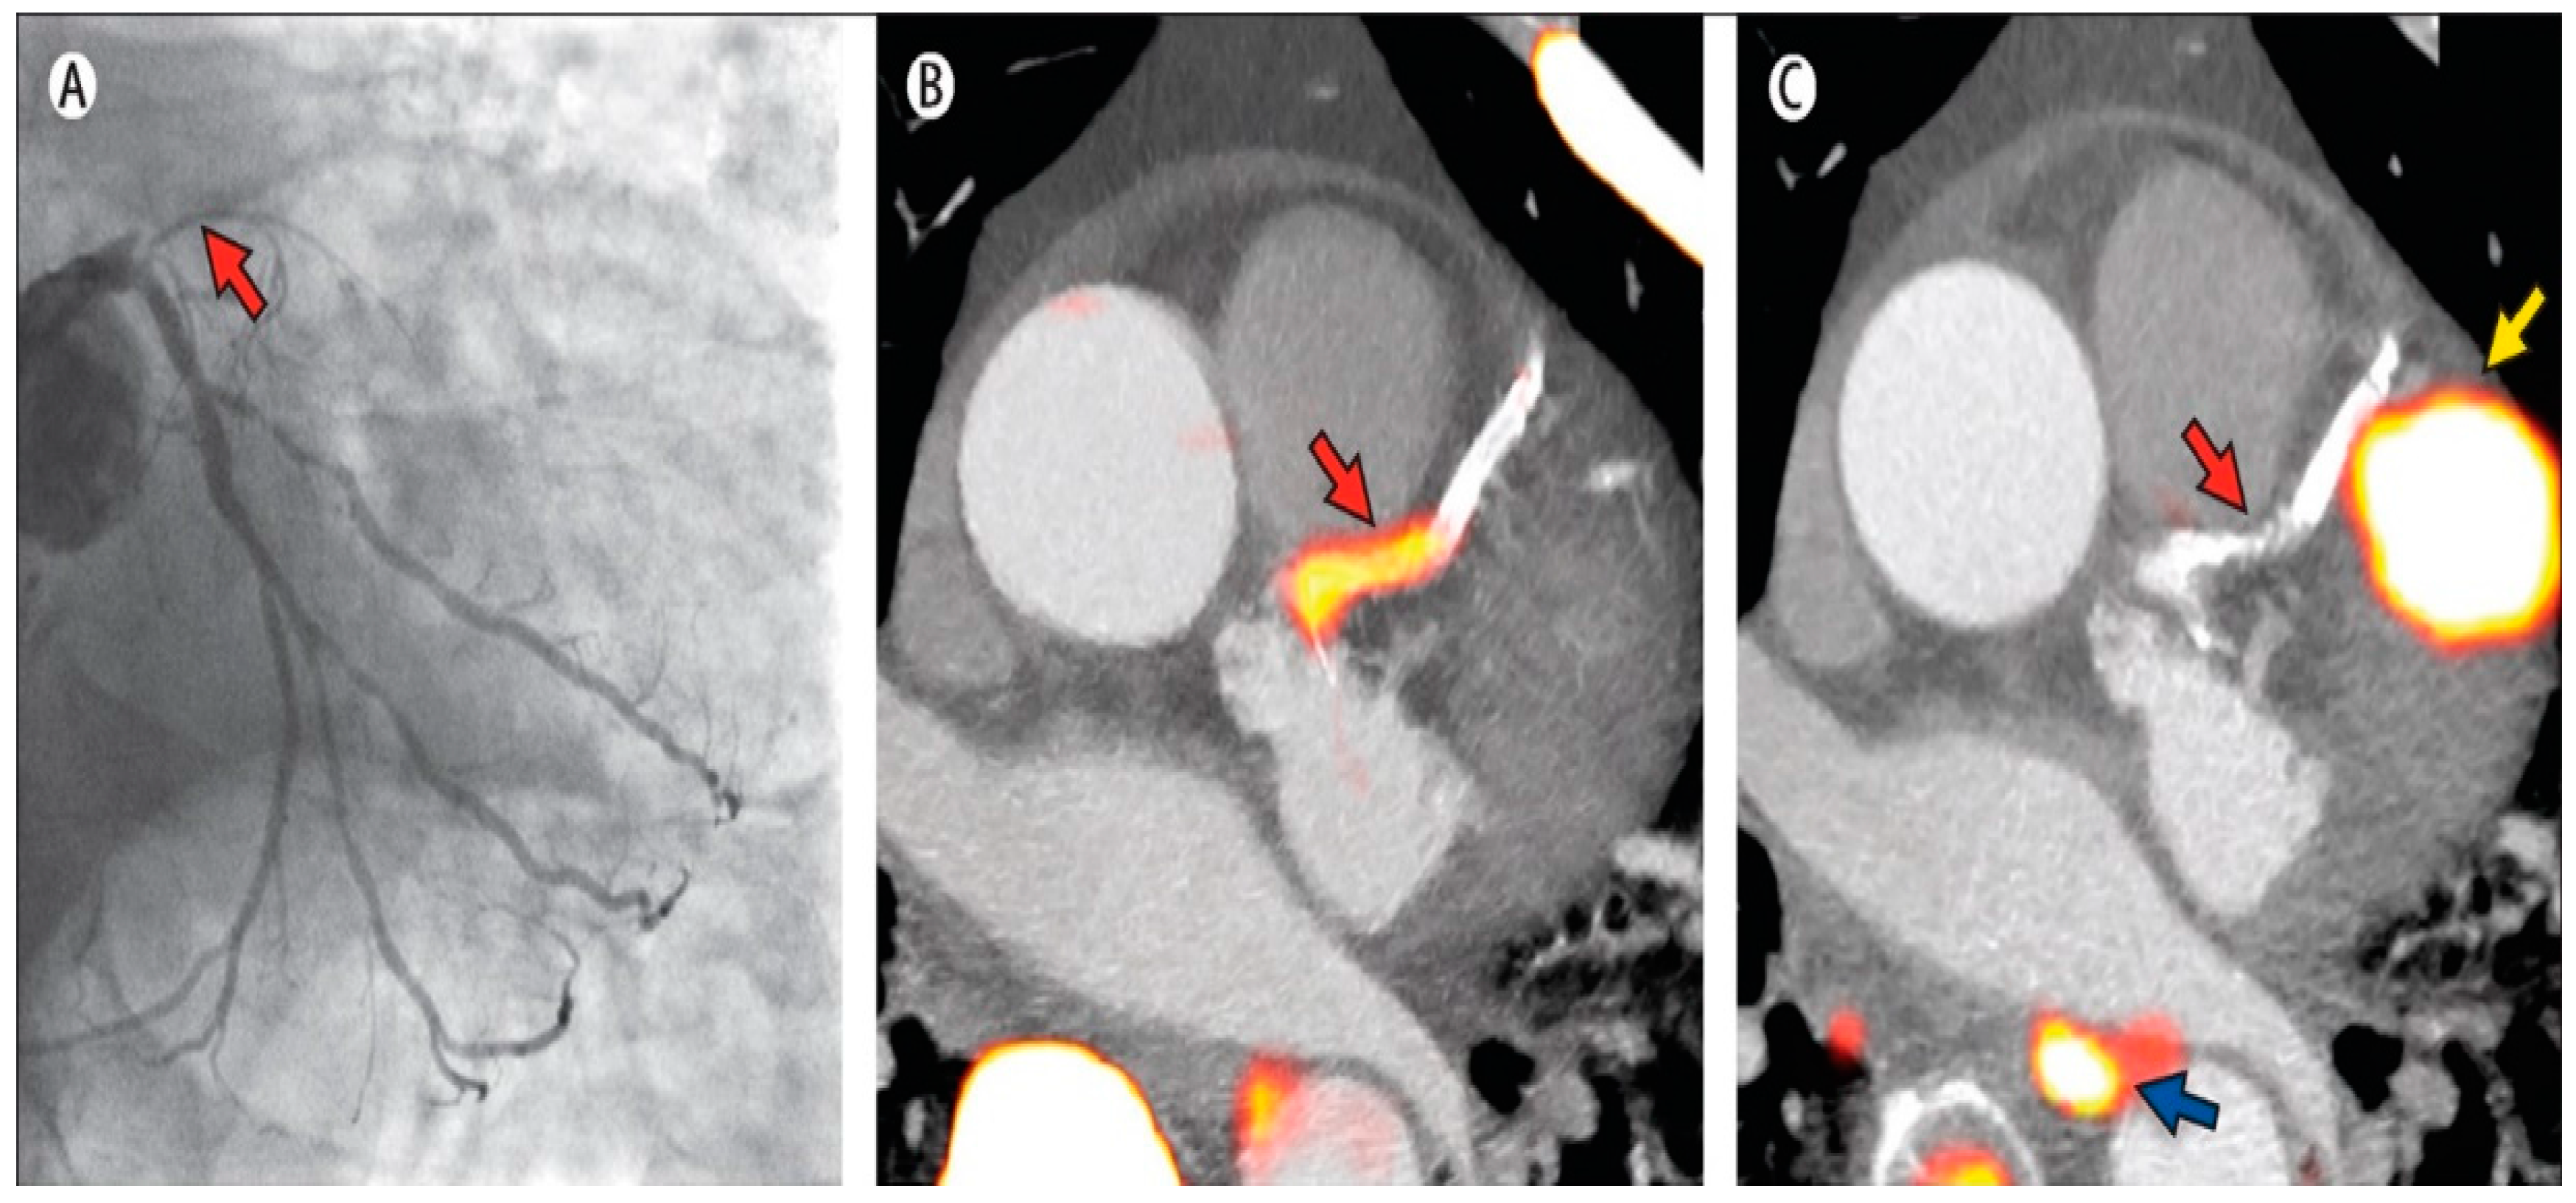

- Graziosi, M.; Nanni, C.; Lorenzini, M.; Diemberger, I.; Bonfiglioli, R.; Pasquale, F.; Ziacchi, M.; Biffi, M.; Martignani, C.; Bartoletti, M.; et al. Role of 18F-FDG PET/CT in the diagnosis of infective endocarditis in patients with an implanted cardiac device: A prospective study. Eur. J. Nucl. Med. Mol. Imaging 2014, 41, 1617–1623. [Google Scholar] [CrossRef] [PubMed]

- Saby, L.; Laas, O.; Habib, G.; Cammilleri, S.; Mancini, J.; Tessonnier, L.; Casalta, J.; Gouriet, F.; Riberi, A.; Avierinos, J.; et al. Positron emission tomography/computed tomography for diagnosis of prosthetic valve endocarditis: Increased valvular 18F-fluorodeoxyglucose uptake as a novel major criterion. J. Am. Coll. Cardiol. 2013, 61, 2374–2382. [Google Scholar] [CrossRef] [PubMed]